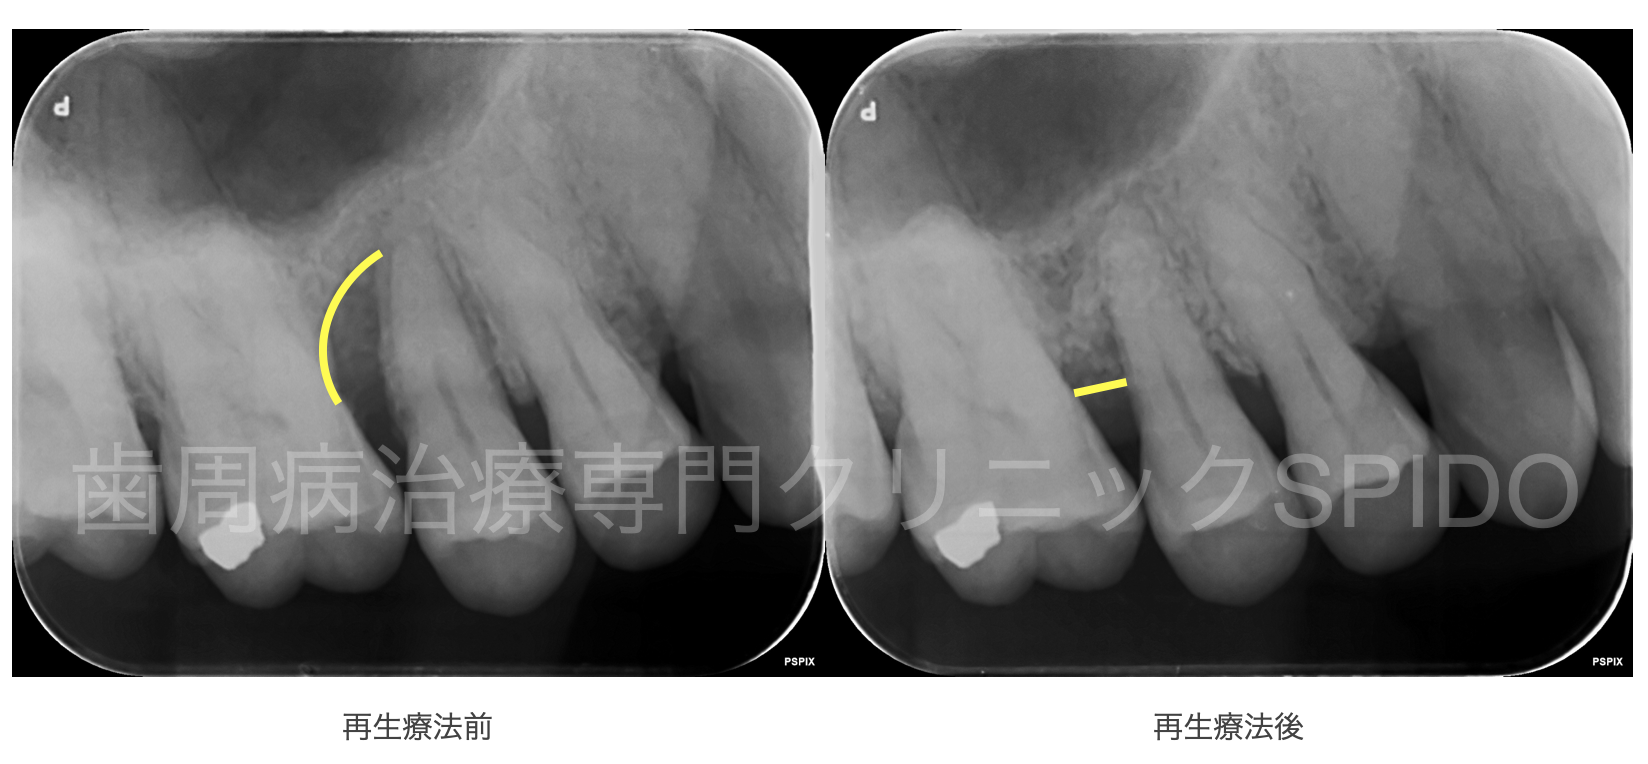

日本初の欧米と同基準の 歯周病および インプラントの 専門治療をお届けします